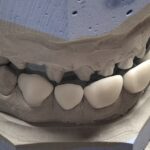

Nos réalisations : Conjointe

Céramique sur Zircone

La zircone présente une très grande résistance à la flexion (plus de 1 400 Mpa).

Translucide, elle reflète la lumière aussi naturellement que l’émail.

Biocompatible elle est garante d’une excellente intégration gingivale.